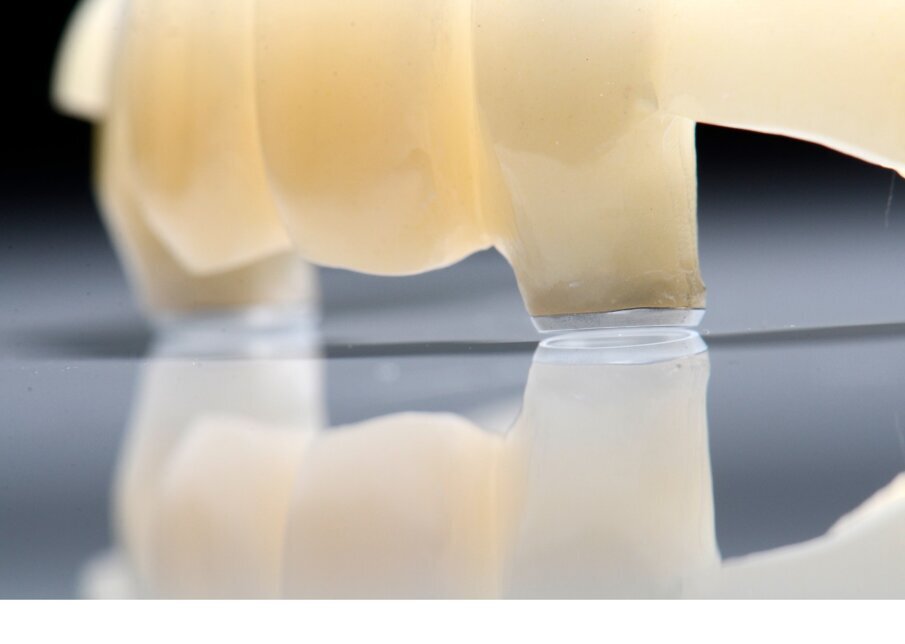

Alloggiamo la dima protesica (Fig. 33), e blocchiamo i transfert con della resina trasparente (tecnica DIL) (Figg. 34, 35). In questo modo possiamo far riposare il paziente in studio dopo appena 35 minuti dall’inizio dell’intervento. La dima protesica, infatti (Fig. 36) con i transfert inseriti viene completata con l’unione degli analoghi ai transfert (Fig. 37). L’insieme così composto viene riadattato sul modello master digitale iniziale (Figg. 38-40) sul quale era stata costruita sia la dima chirurgica che la dima protesica come anche il provvisorio. Gli analoghi vengono bloccati sul modello con resina trasparente (Figg. 41-43). Alloggiamo il provvisorio sul modello master digitale così ottenuto (Figg. 44, 45).

Fig. 36 - Dima protesica e transfert bloccati.

Fig. 37 - Dima protesica e transfert bloccati.

Fig. 38 - Riposizionamento sul modello master.

Fig. 39 - Alloggiamento definitivo

Fig. 41 - Resina trasparente e analoghi bloccati.

Fig. 42 - Finestre d’ispezione.

Fig. 43 - Analoghi bloccati sul modello master iniziale.

Il risultato sarà quello di ottenere un modello master già relazionato all’arcata antagonista e soprattutto un modello che contiene la posizione esatta degli impianti appena inseriti. Questo rappresenta il cuore della tecnica DIL, evitiamo impronta post-chirurgica, evitiamo la registrazione di una nuova dimensione verticale e realizziamo il modello di lavoro in pochissimo tempo.